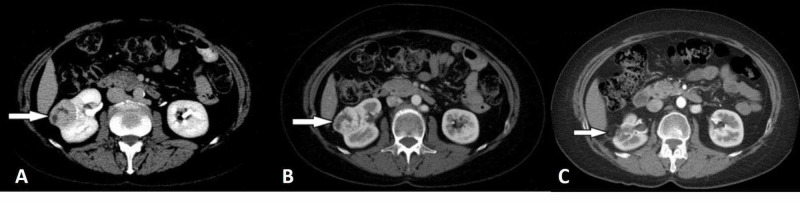

Figure 1. Clear cell RCC example from the source review. The corticomedullary and excretory phase CT images show the classic hypervascular pattern with later washout that makes radiologists lean toward clear cell RCC rather than papillary RCC. Source:

Morshid et al., Figure 1

, Creative Commons Attribution License.2

| Clear cell-leaning pattern24 | Avid corticomedullary hyperenhancement, heterogeneity, necrosis, washout, pseudocapsule, or venous invasion | This is the classic aggressive-looking RCC pattern and the subtype most people picture first |

Clear cell RCC is the classic hypervascular subtype. It often enhances similarly to cortex in the corticomedullary phase, can look heterogeneous, and is more likely to show necrosis or venous invasion in aggressive cases.2 Papillary RCC usually sits at the opposite end of the spectrum: more hypovascular, often more homogeneous when small, frequently T2-dark, and sometimes hyperattenuating before contrast, which is why it can drift toward cyst or AML confusion.25 Chromophobe RCC often falls in between, with more intermediate enhancement and enough overlap with oncocytoma that imaging may stay suggestive rather than pathology-level definitive.24